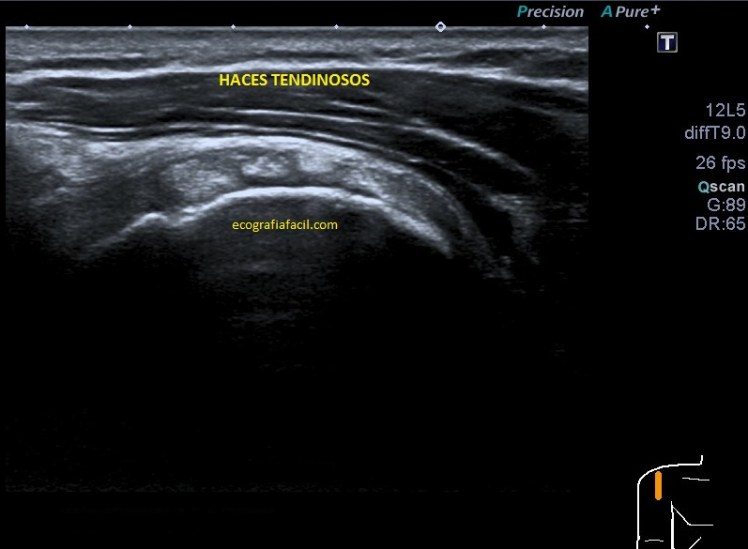

Vamos a partir de la normalidad y te vienes a ver ahora la patología que hoy nos ocupa, mira. En ocasiones podemos encontrarnos la imagen patológica que indica luxación del tendón, imagen 2. Es un corte en Eje corto. Ves la corredera bicipital vacía, el tendón fuera de su localización habitual, hacia medial, como es habitual, pero conservando la ecoestructura.

La imagen número 3 corresponde al corte en eje largo, mucho cuidado, siempre que tengamos el tendón del bíceps luxado, este se irá hacia medial, por eso, en eje largo vamos a encontrar la ecoestructura ligeramente hacia la axila, hacia medial.

Efectivamente, verás que bordeando el tendón existe una mínima cantidad de líquido que está envolviendo u ocupando la vaina del tendón, se ve anecoico y efectivamente es cierto, si lo has visto, enhorabuena, a parte de la luxación, esa es la otra semiología evidente que podemos ver en la imagen 2.